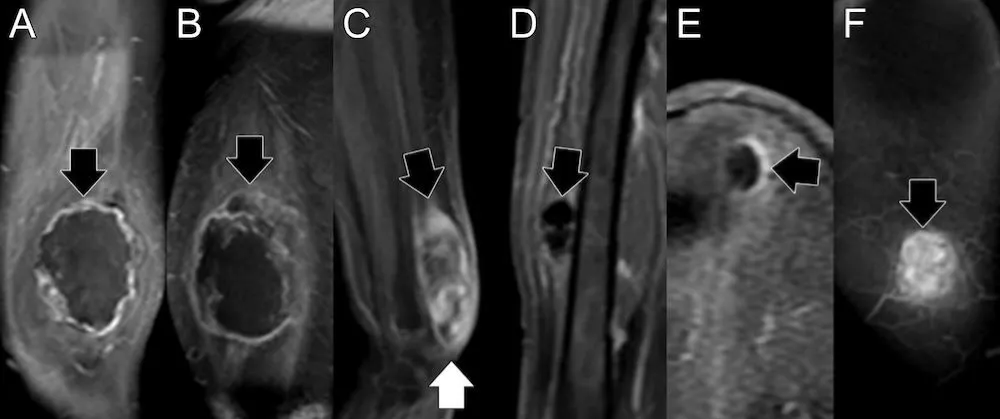

CE-SWI and PWI/DCE patterns

Figure 2 presents RMS’s observed CE-SWI and PWI/DCE patterns at BL and PS. At PS, 50% of responders displayed a Complete Ring pattern (p = 0.5578), Capsular pattern (p = 0.6065), and TIC Type 2 (p = 0.6065). Partial/non-responders mainly presented CE-SWI Incomplete Ring and No Blooming patterns, PWI/DCE Unipolar and Solid Enhancement patterns, and TIC types 3 and 5.

Figure 2: CE-SWI and PWI/DCE patterns were observed in RMS at baseline and PS. At PS, responders displayed a CE-SWI complete ring, a PWI/DCE capsular enhancement, and a TIC type 2 in 50% of cases.

Although it has been demonstrated that marginal-to-no significant differences were found in semiquantitative analysis, including PWI/DCE time-to-peak enhancement, maximum enhancement, and time-intensity curve types between RMS and sinonasal carcinomas in adults, the ADCs of sinonasal RMS can be significantly lower than those of sinonasal carcinomas [26]. Our findings also indicated that semiquantitative PWI/DCE metrics were unable to distinguish responders from partial/non-responders. Nonetheless, using morphologic and qualitative PWI/DCE patterns, half of the RMS responders display a PWI/DCE Capsular pattern and TIC type 2 at PS. In contrast, partial/non-responders mostly display Unipolar and Solid Enhancement patterns with TIC types 3 and 5 (Figure 2). Representative examples of these morphological patterns are shown in Figure 8. These findings agree with the previously reported Capsular and TIC type 2 PWI/DCE patterns observed in UPS responders in the post-radiotherapy assessment [17].

Download Image

Figure 8: Representative pre-surgical PWI/DCE morphologic patterns of response in RMS patients and their correlation with PATE. A. Capsular with 90% PATE. B. Solid Enhancement with 5 % PATE. C. Unipolar with 70% PATE. PATE: pathology-assessed treatment effect.